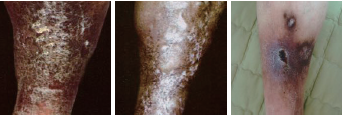

2. 치료전후 사진